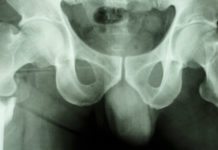

Resultaten, som publicerats i Archives of internal medicine, visar att kvinnor som någon gång använt loopdiuretika inte löpte någon högre risk att få frakturer. Forskarna kunde inte heller se någon skillnad i bentäthet mellan de två grupperna. Däremot fanns en något högre risk att drabbas av fraktur bland de kvinnor som behandlats med loopdiuretika under en längre tid.

Författarna till artikeln skriver i en kommentar att det kan finnas en koppling mellan sämre hälsa överlag och användning av loopdiureika som också kan förklara fynden.